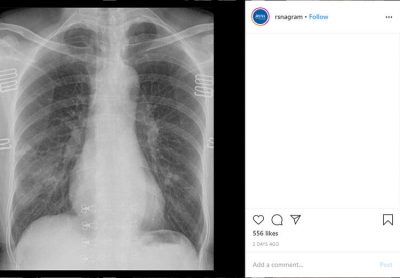

Corona Virüsle İlgili Korkunç Gerçek Ölen Hastanın Röntgeni Sayesinde Ortaya Çıktı

Dünyayı tehdit eden corona virüs neredeyse tüm dünyaya yayıldı